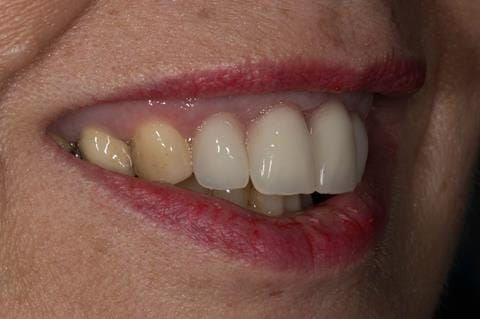

- High smile line showing gum above gingival zeniths of upper front teeth when smiling. Aesthetic failure of the upper four incisors with inflammation of the gingivae and mis-match of the gingival zenith levels.

Following consultation and second discussion appointment the patient chose to have option 3 namely, a maxillary cobalt chromium based partial denture/protective occlusal splint. The clinical situation and treatment process is shown in detail below with photographs. The patient was successfully rehabilitated with this and her quality of life considerably improved. The clinical work was provided by Finlay and the technical work by Rowan.